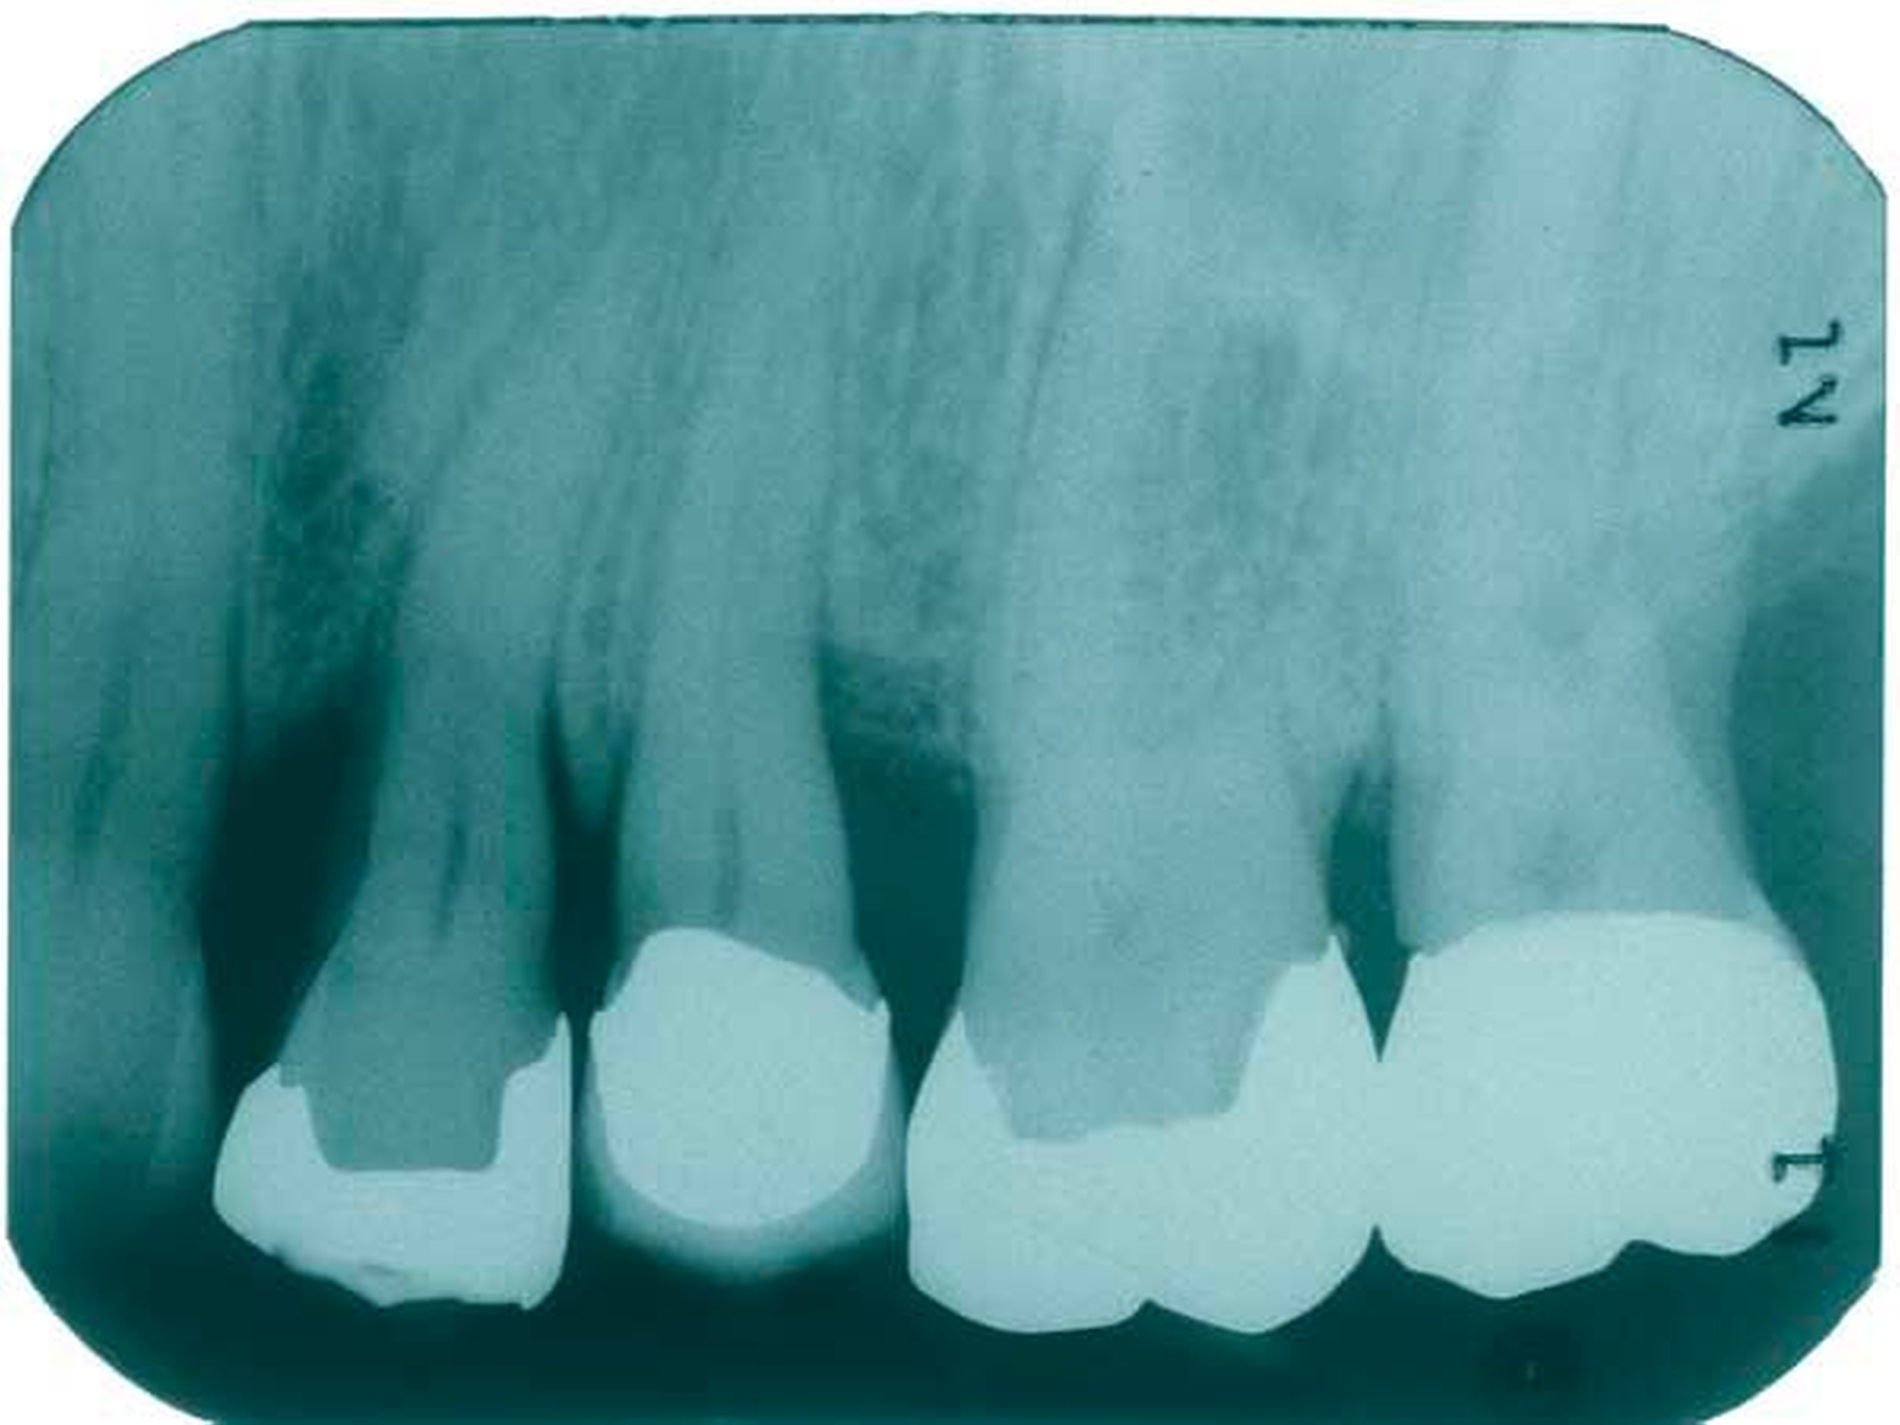

Im Mittel führt eine subgingivale Instrumentierung zu einer Reduktion der Taschensondierungstiefen von etwa 1,2 mm [Van der Weijden and Timmerman, 2002]. Diese Reduktion der Sondierungstiefe sowie die Veränderung des klinischen Attachmentlevels sind deutlich von der Sondierungstiefe vor Therapie abhängig [Hunt & Douglass, 2002] (Tabelle 1). In Situationen mit geringen Sondierungstiefen unter 3 bis 3,5 mm sollte auf eine energische subgingivale Instrumentierung verzichtet werden, um einen Verlust von Attachment zu vermeiden [Lindhe et al., 1982].